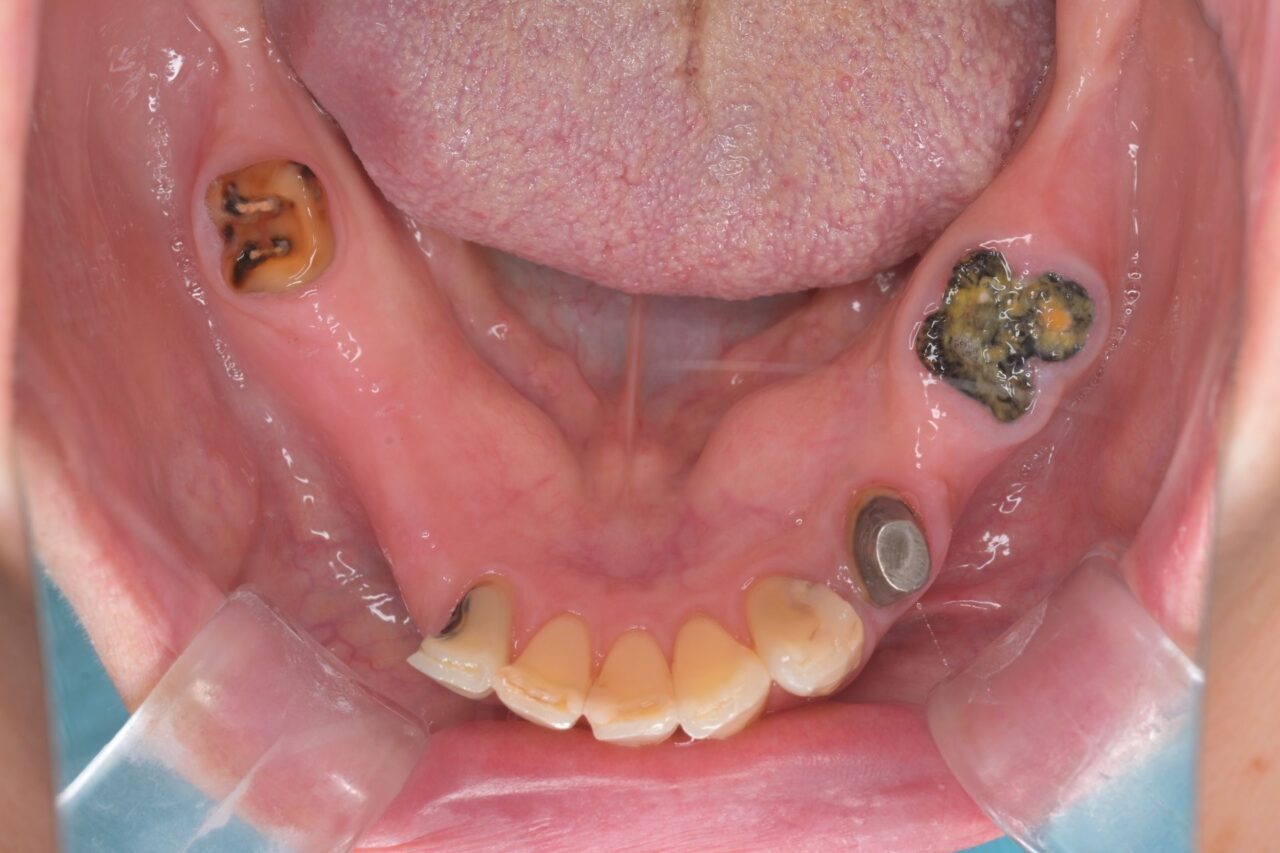

下面

大きな虫歯が放置されていた入り、かぶせ物が無くなって放置されていたり、様々な問題があります。保険治療で済ませようと思うと入れ歯は確定です。